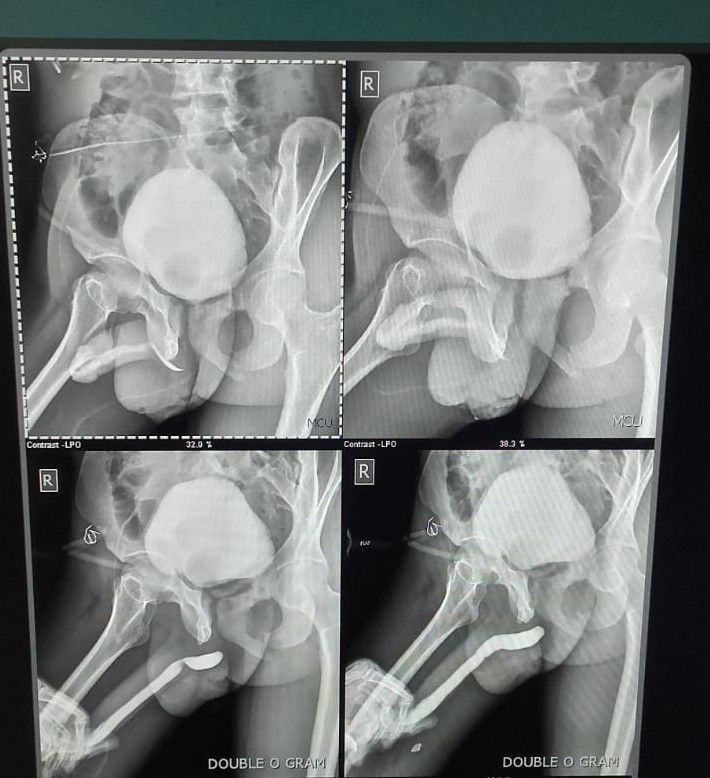

Urethral trauma

Radiology

Urology

Radiographer

Fluoroscopy